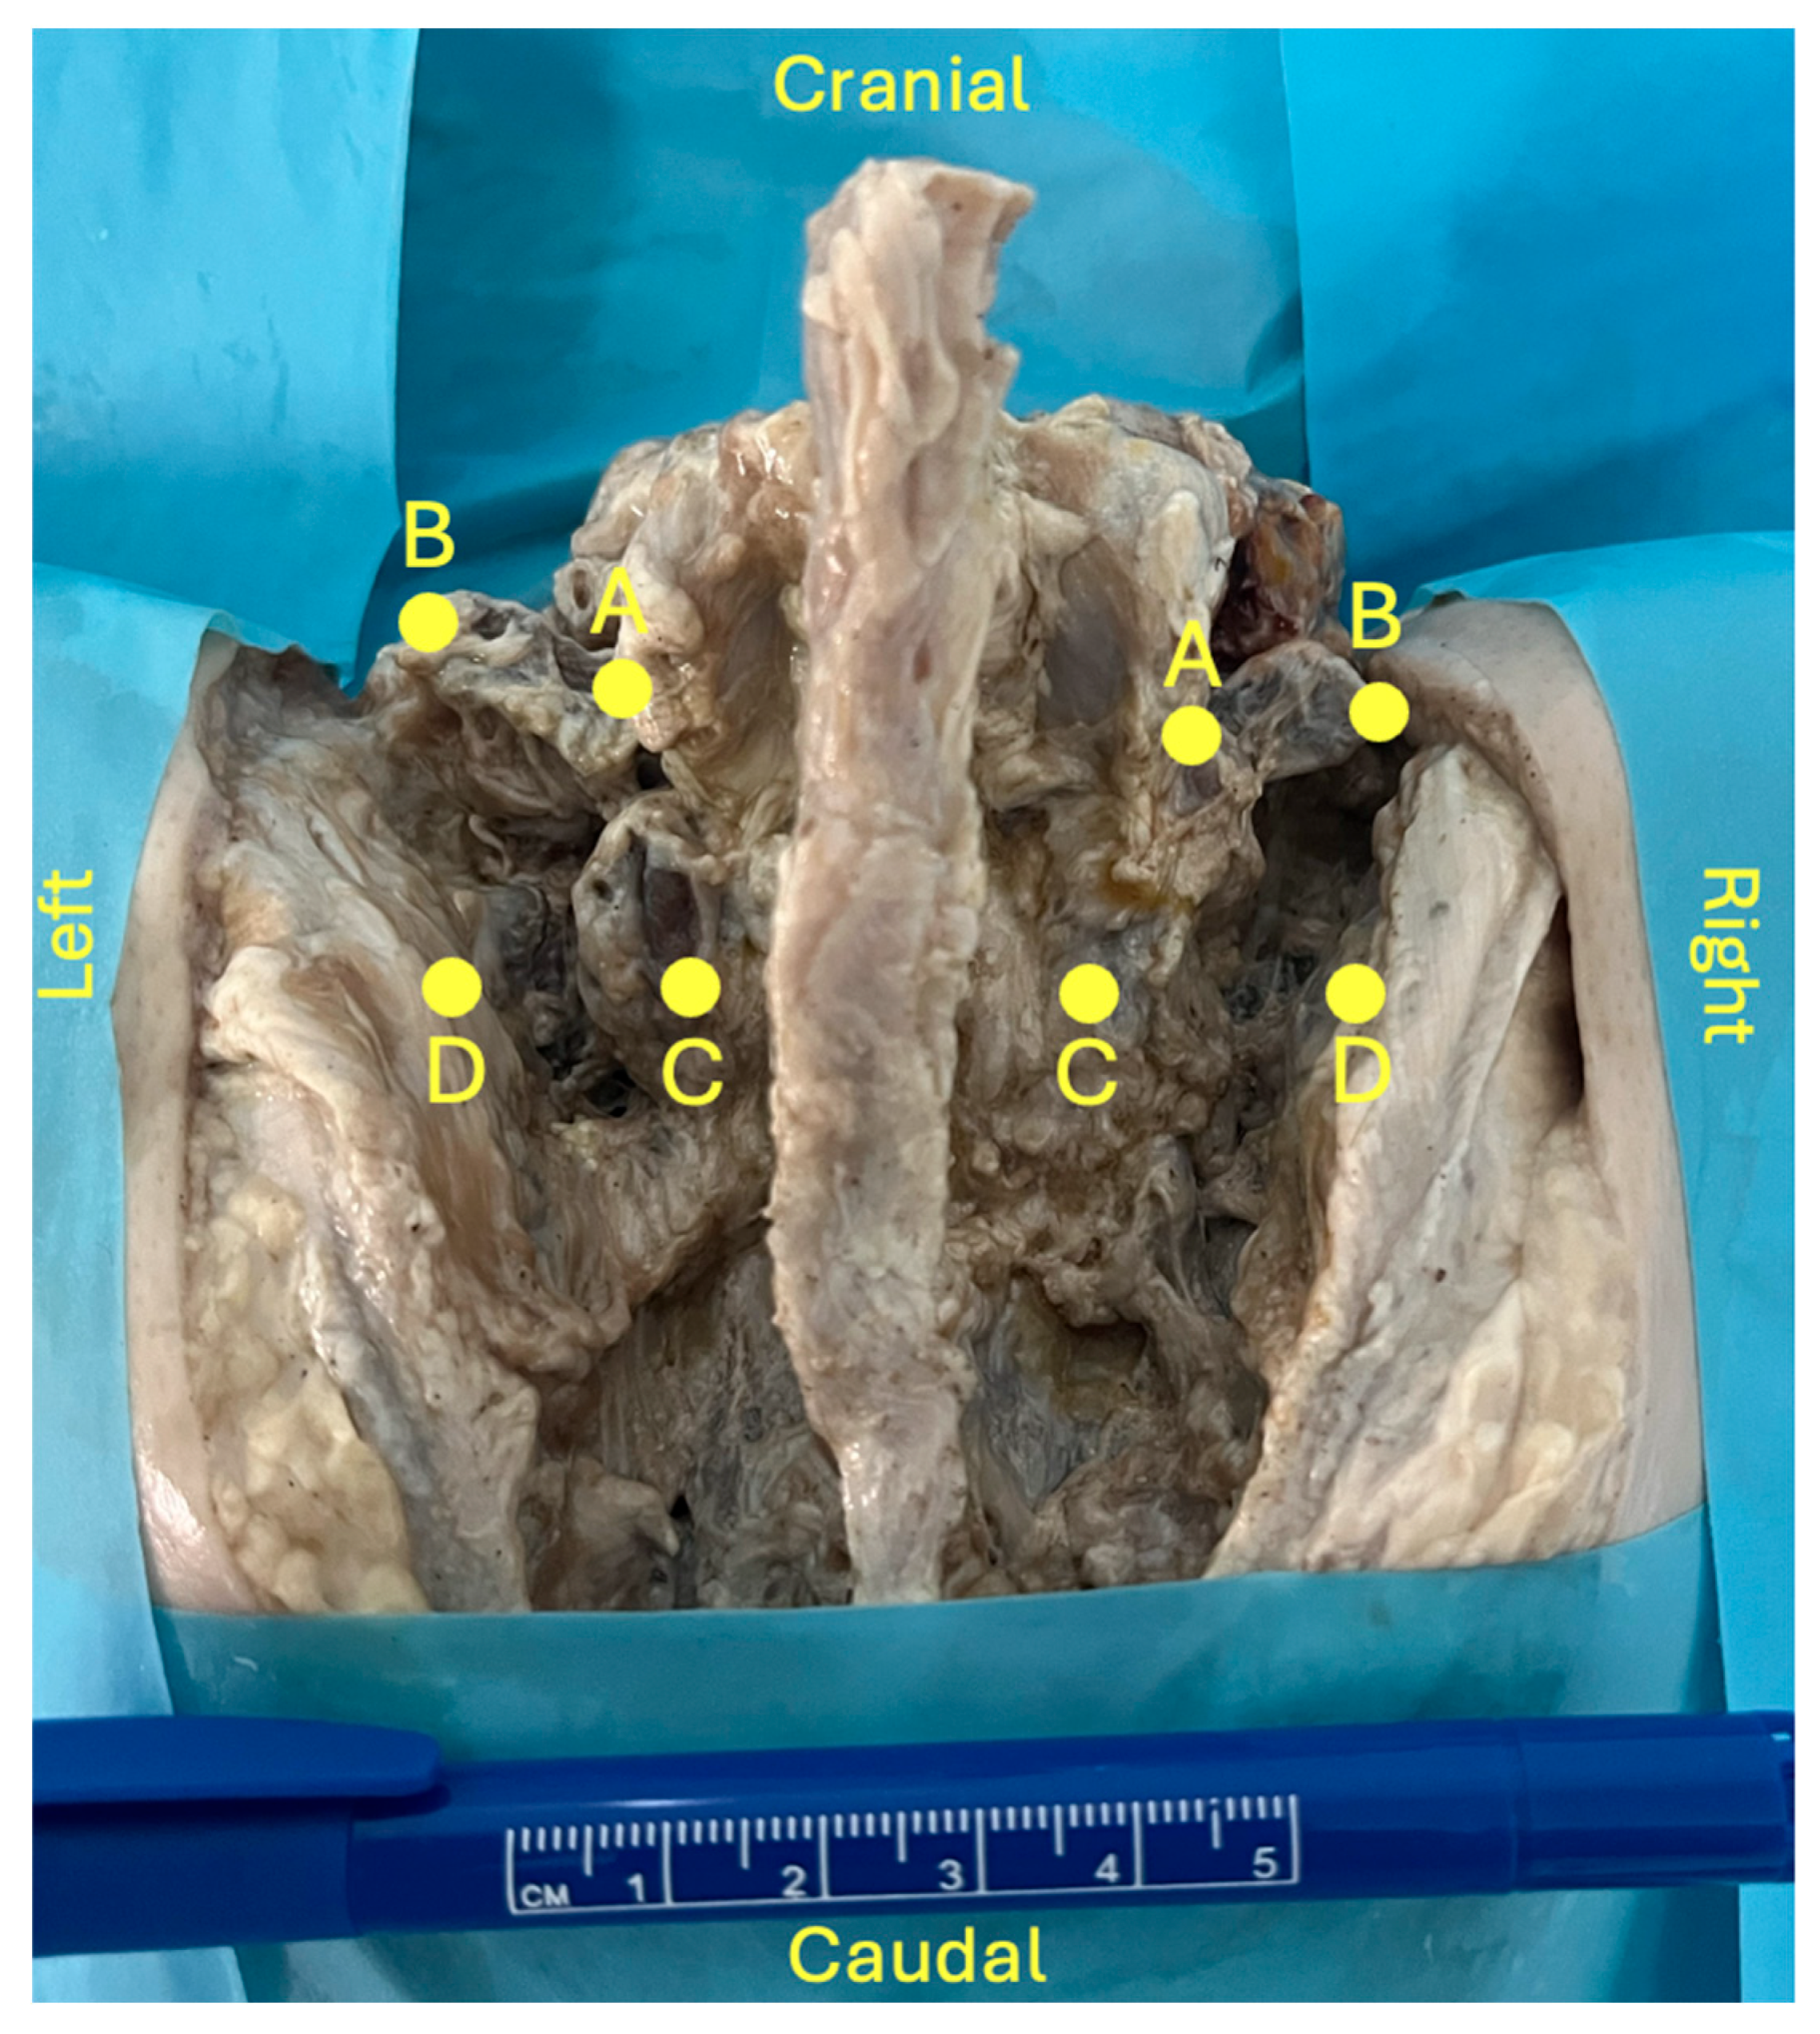

A standard midline posterior approach to the lumbosacral spine was performed to expose the posterior elements from L4 to S2. Care was taken to preserve bony structures as well as the native position of ligamentous and neurovascular components. Four predefined anatomical landmarks (points A-D) were identified (Figure 1):

• Point A: base of the L5 transverse process (TP)

• Point B: tip of the L5 TP

• Point C: inferior tip of L5 inferior articular process

• Point D: medial margin of the iliac crest at the level of point C

Using these landmarks, four distances were measured (A-B, C-D, A-C and B-D) using a ruler graduated in millimeters.

Figure 1. Lumbosacral region dissection (posterior view). For demonstration purposes the zygapophyseal joint was opened on the left side. A: base of the L5 transverse process (TP); B: tip of the L5 TP; C: tip of L5 inferior articular process; D: medial margin of the iliac crest at the level of point C.